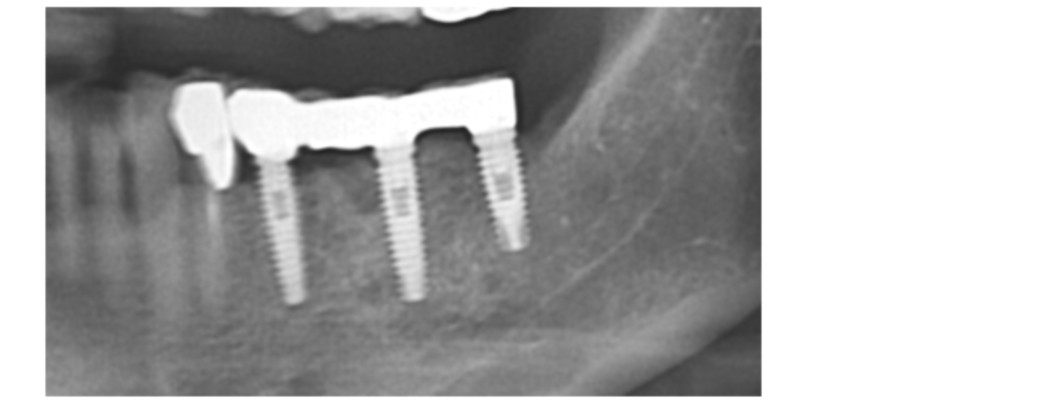

▶ 상악과 하악의 명확한 교합을 위해 적정한 각도로 임플란트를 식립하여 정교하고 강도 높은 보철 제작으로 실제 사용 시 불편함을 제거합니다.

02 임플란트의 강력한 골결합력

음식을 씹을 때 흔들리거나 이물감이 들지 않도록 임플란트가 뼈와 강하게 결합되는 것이 중요한데요. 이는 임플란트의 수명과 직결되는 요소로 친수성이 높은 칼슘 임플란트를 사용하여 임플란트와 치조골간 골 생성이 치밀하고 우수하여 강한 골 결합력을 유지하도록 해야 합니다.

▶ 3D CT를 통한 정밀 검사와 리뷰로 관리 계획을 세우고 관리하여 관리 시 손실이나 응급 사태에 대한 우려 없이 만족적인 임플란트 관리가 가능합니다. 뿐만 아니라 조직 손실이 매우 적어 복원과 재활이 매우 빠릅니다.